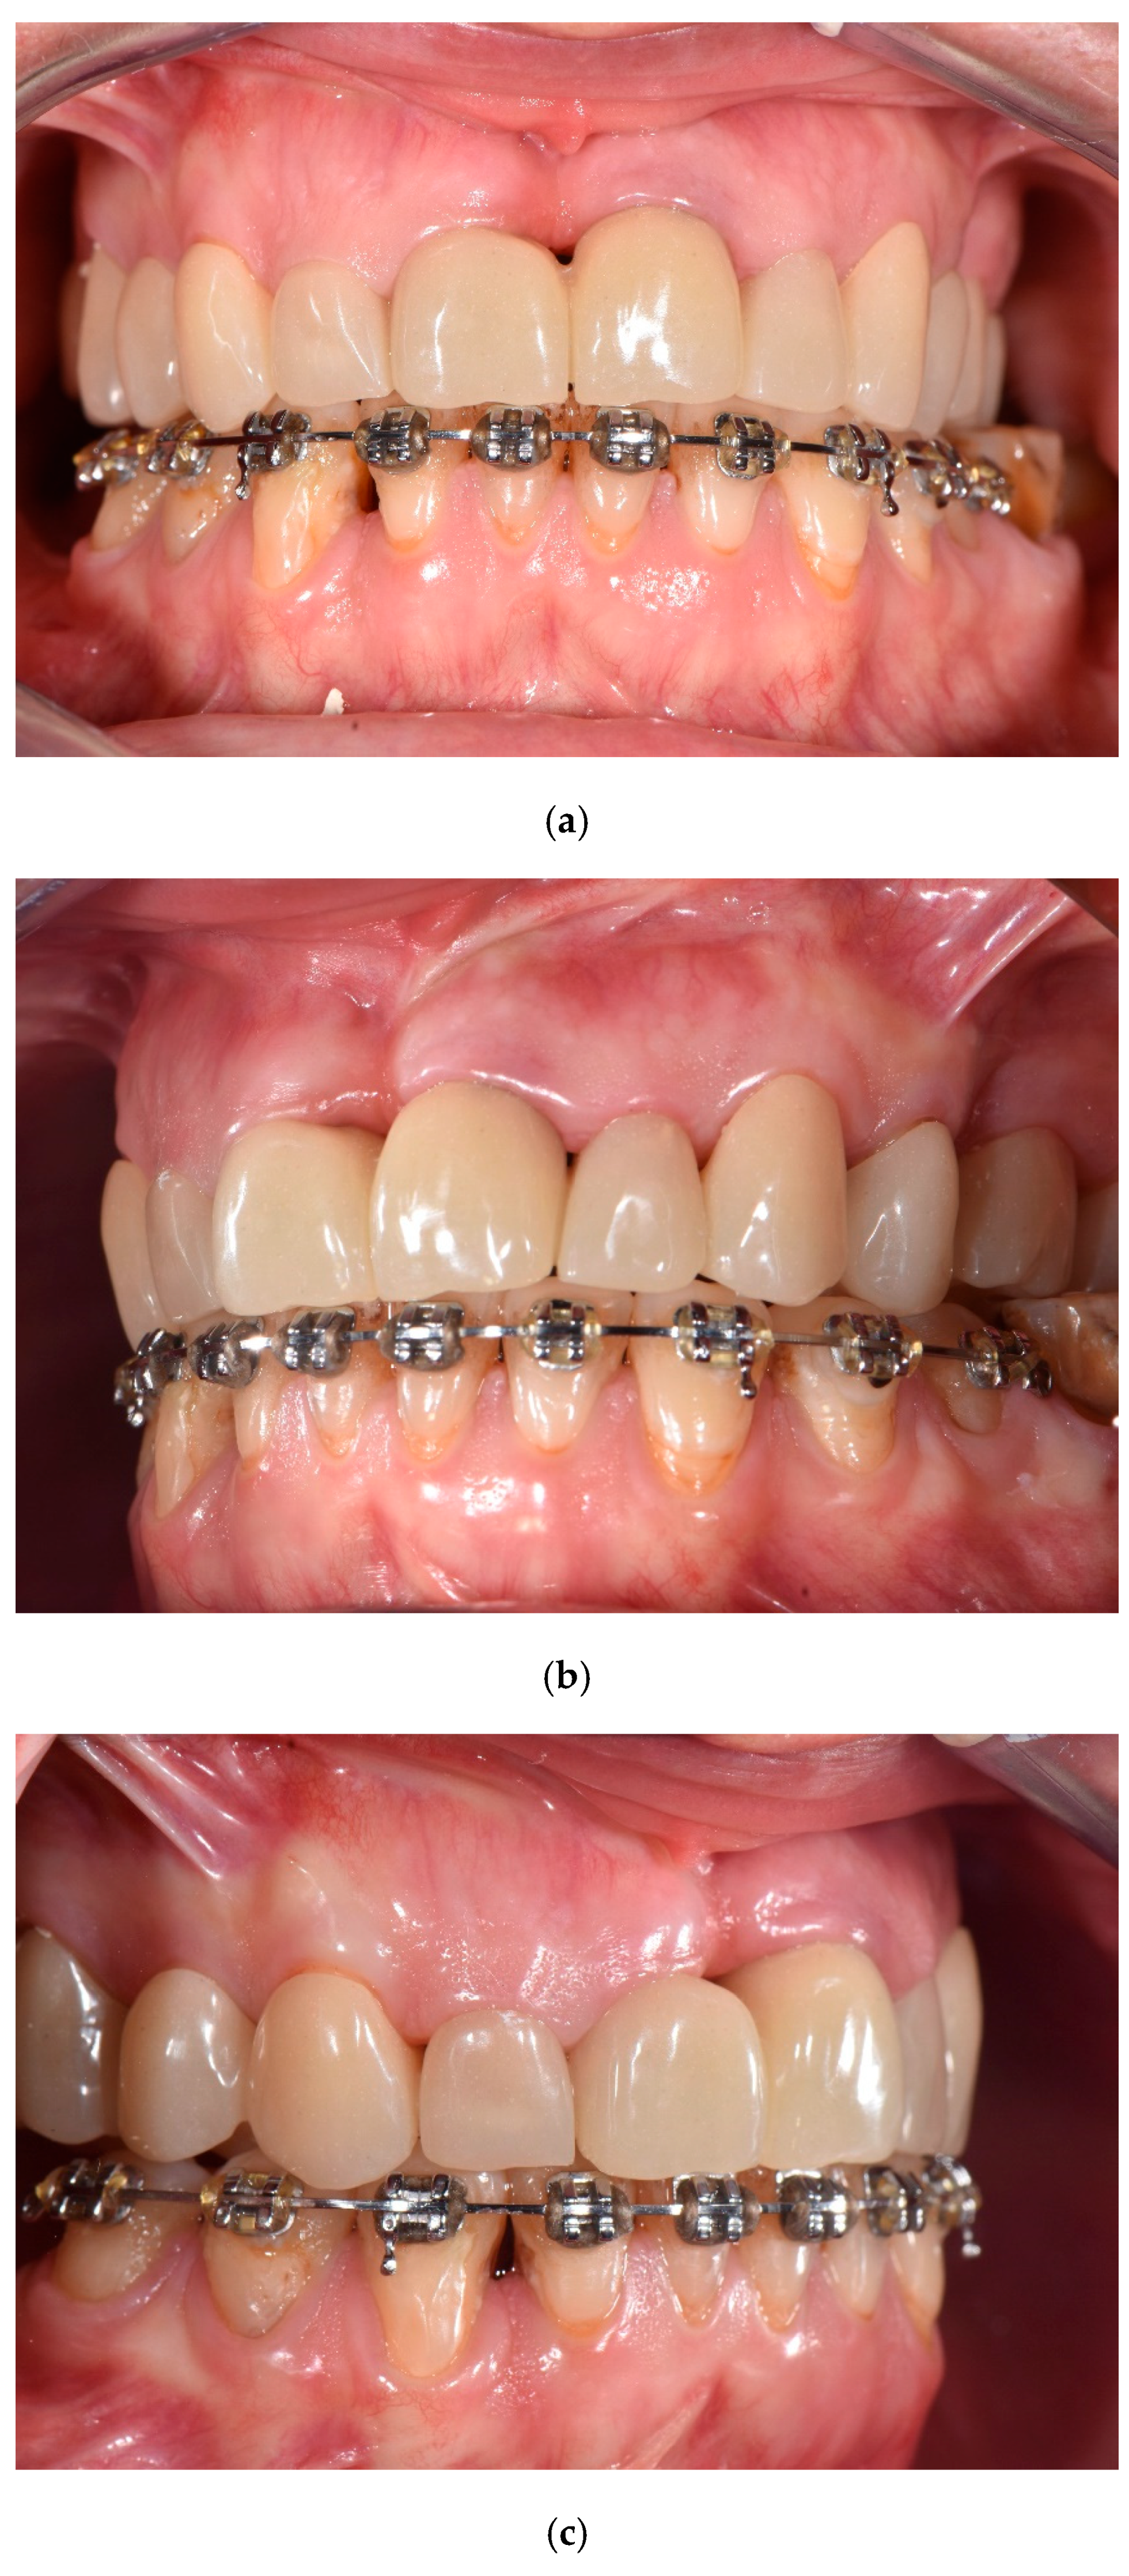

2.3. Prosthetic Phase

2.4. Surgical Phase